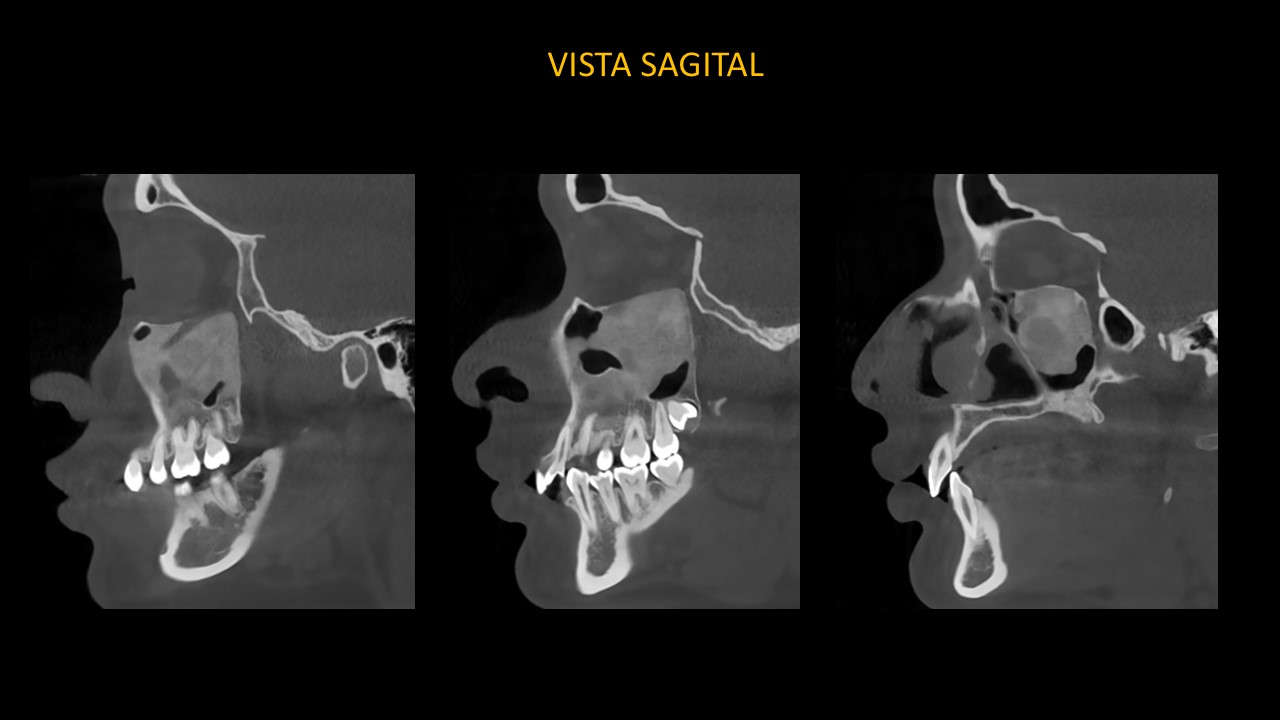

Figura 4

En las vistas sagitales (Figura 4), podemos confirmar expansión de la cortical basal de cavidad orbitaria y la extensión de la lesión hacia la zona peri radicular de las piezas 23, 24, 25, 26, 27.